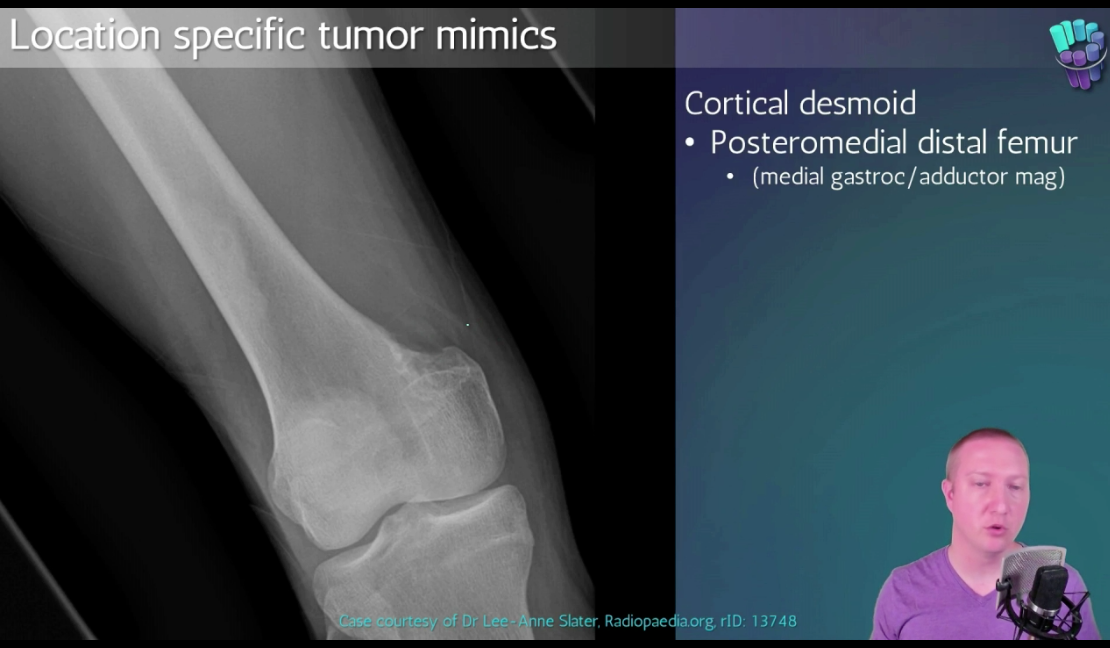

Segond fracture

Dr Subhan Iqbal◉ and Assoc Prof Frank Gaillard◉◈ et al.

Segond fracture is an avulsion fracture of the knee that involves the lateral aspect of the tibial plateau and is very frequently (~75% of cases) associated with disruption of the anterior cruciate ligament (ACL). On the frontal knee radiograph, it may be referred to as the lateral capsular sign.

The classical appearance of a Segond fracture is that of a curvilinear or elliptic bone fragment projected parallel to the lateral aspect of the tibial plateau. This has been referred to as the lateral capsular sign 1, which is best seen on the anteroposterior view of the knee.